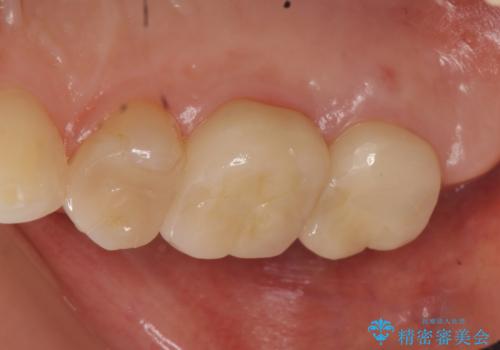

- 右上6、7の詰め物、被せ物を治して欲しいといらっしゃった方の症例です。

右上6は虫歯を除去し、右上7は再根管治療後、オールセラミッククラウンによる補綴を行いました。

今回用いたオールセラミッククラウンは、ジルコニアフレームという白い素材の上にセラミックを盛っているため審美性が非常に高いのが特徴です。

またジルコニアは人工ダイヤモンドの材料にも使われているほど高い強度を持っており、そのためオールセラミッククラウンは審美性だけでなく、奥歯やブリッジの補綴も可能とするクラウンです。